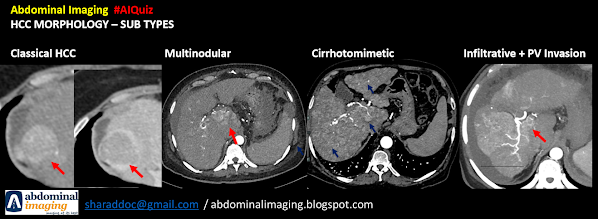

Macrosocpic Subtypes:

- Nodular: encapsulated

- Multinodular: Aggregation of multiple small nodular type

- Massive : Large tumor with irregular demarcation

- Mosaic Architecture: tumor nodules separated by fibrous septations, hemorrhage, necrosis or fatty metamorphosis.

- Cirrhotomimetic / infiltrative : Cirrhotic like HCC or confluent multinodular with a "macroscopic appearance of innumerable permeating tumor nodules that resemble cirrhosis".

It can evade clinical and imaging. Usually poorly differentiated or undifferentiated

-Diffuse